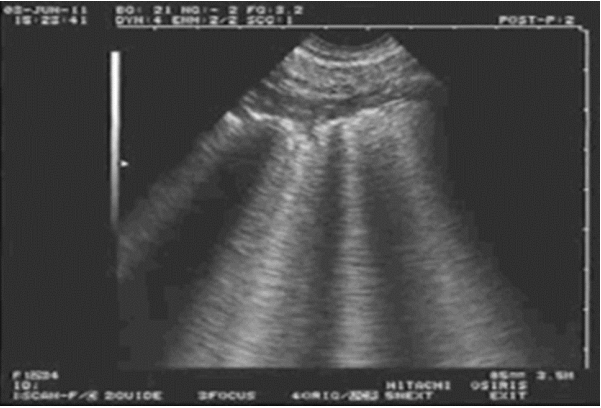

A线的出现代表胸膜线以下含气良好。胸膜滑动征消失的原因有多种,例如在胸膜粘连、肺不张、ARDS、重症感染后胸膜增厚等情况下可能会出现。2012年,重症医学相关研究人员发表的专家组文章指出,在怀疑气胸时,对胸膜滑动征的评估是起始因素,也是关键因素,对气胸的阴性预测值可达100%。也就是说,如果看到了胸膜滑动征,则可以排除气胸诊断;如果没有看到胸膜滑动征,还需进一步明确是否合并其他肺超征象,从而明确诊断。下列超声图像1中可见胸膜线随着呼吸运动而来回滑动,但在超声图像2中却未见胸膜线来回滑动。我们呼吸时,胸壁会被向上推开,当胸膜滑动消失时,可见胸膜线随着呼吸、肺扩张及胸壁向上移动。当看到滑动征消失时,需考虑气胸的可能。

超声图像1(正常胸膜滑动)